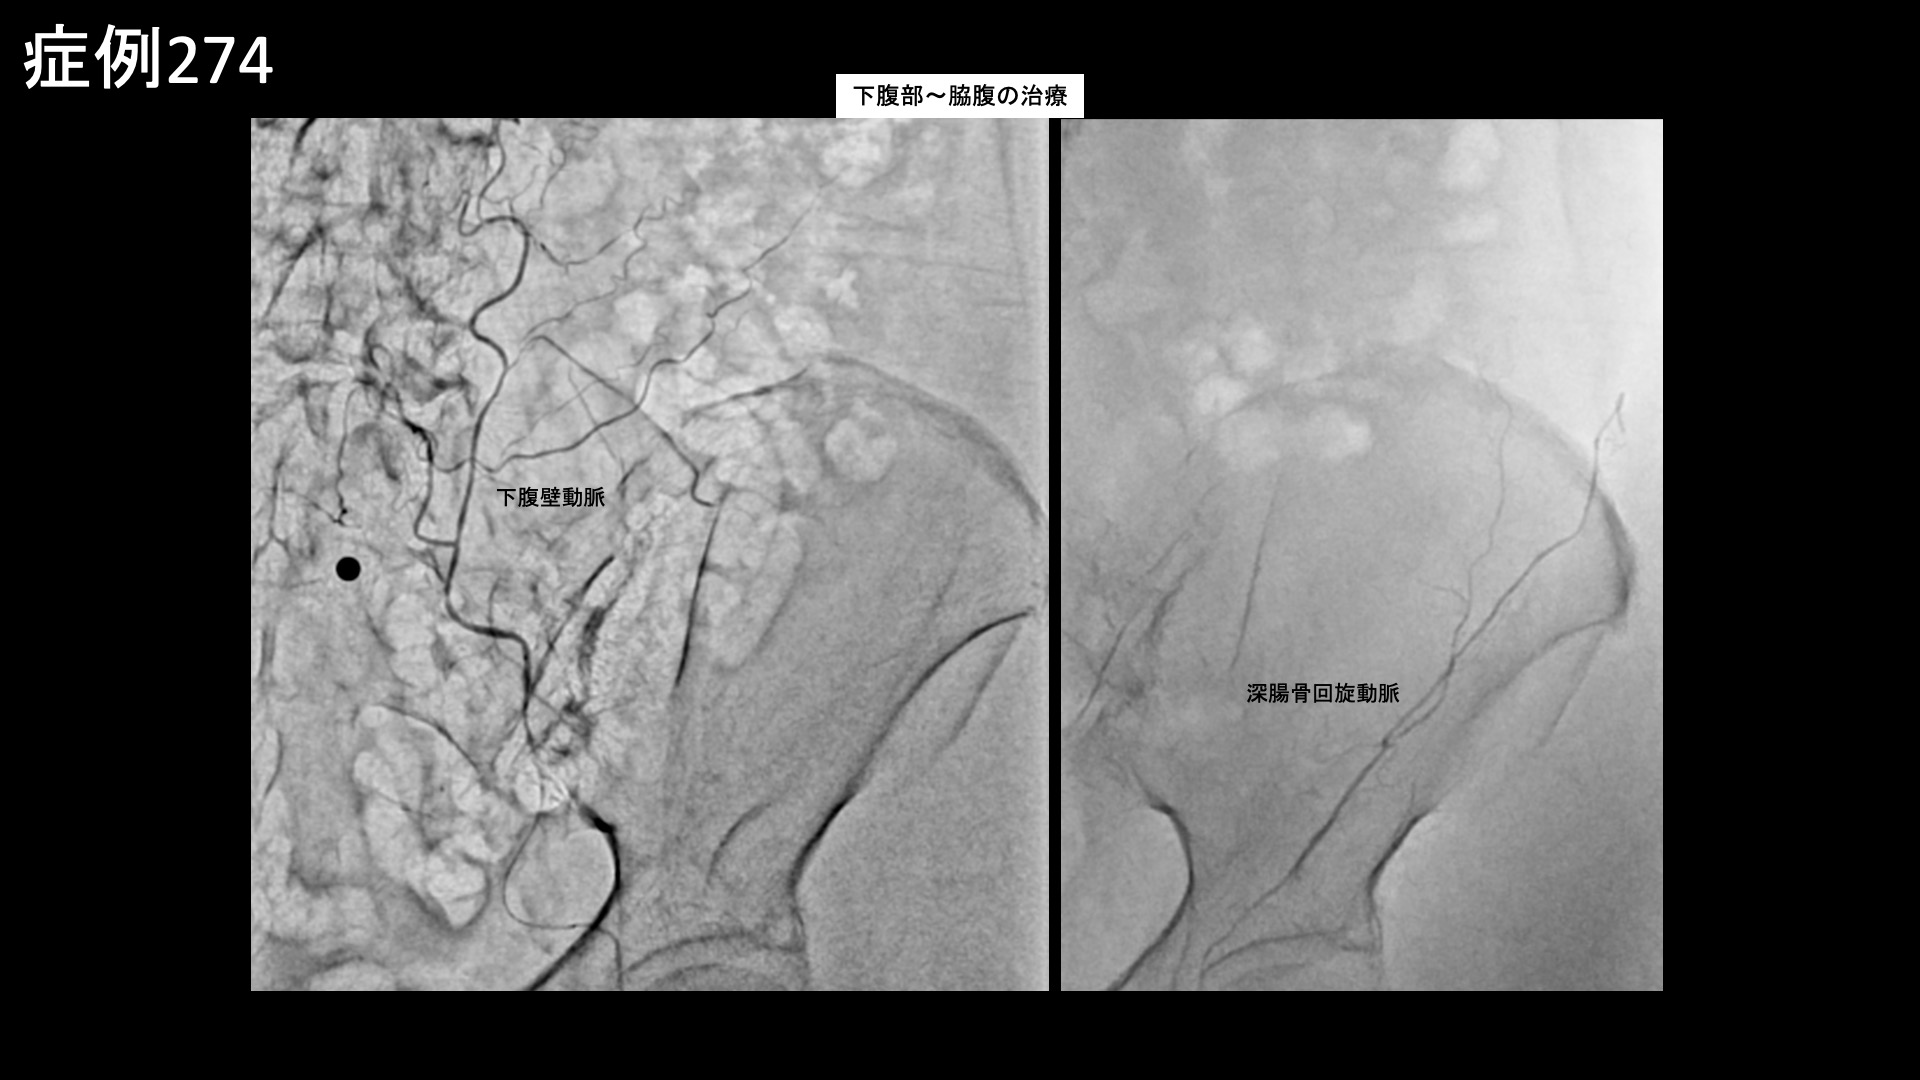

その他:帯状疱疹後など 【70代:女性】それほど目立たない発疹だったのにこんなに痛くなるなんて・・下腹部、脇腹に生じた発症1ヶ月半の帯状疱疹後神経痛 2026.03.27 鴨井院長による動画解説 受診までの経過 11ヶ月前から左肩が痛むようになり、整形外科や鍼灸院など複数の施設に通いました。3ヶ月くらいで治ると言われ、注射治療などを受けましたが、半年くらいでようやく少しおさまったものの腕はいっこうに上がりませんでした。それどころか右肩も痛くなり、夜間痛や起床時痛にも見舞われ、朝から気力を奪われてしまい、洗髪・洗顔など日常生活にも大きく支障をきたすようになりました。元々は毎日出かけたい性分でしたが、最近はどこにも行きたくなくなってしまうほどでした。 診察時の所見 発症1ヶ月半の帯状疱疹後神経痛であり、その他特段の治療抵抗要因(投薬治療を要する鬱の合併、極端な体重減少や『るいそう』、極端な活動性の低下や社会/家族との断絶、破局的思考、高度の貧血その他)は見られないことから治療による改善が見込まれました。治療適応と判断し、モヤモヤ血管(病的新生血管)に対する運動器カテーテル治療(微細動脈塞栓術)を受けていただきました。 治療の所見 下腹部の主要責任血管である下腹壁動脈、脇腹の主要責任血管である深/浅腸骨回旋動脈、さらに背中~脇腹に分布する腰動脈を順に治療しました。それぞれ一定の再現痛を確認しました。その他複数個所の治療を行い終了しました。 *再現痛とは、薬液投与時に普段の痛みが一定程度再現される現象です。責任血管の同定のための参考とします。 治療後の経過 治療後2週間で寝られるようになりました。背中の痛みはあまり感じなくなりました。治療後1ヶ月半、7-8割程度の痛みは改善しました。鎮痛薬を服用する頻度も減りました。治療後3ヶ月、痛みはほぼ消失しました。ゼロではないものの違和感程度になりました。腹部の痛みは治りにくいと聞いていたので、早く治療を受けて良かったと言われました。 当初の発疹はそれほど激しくはありませんでしたが、特に腹部の症状は強く感じていました。下腹部や脇腹は比較的敏感な部位であり、激しい発疹でなくても強くしつこい嫌な痛みが持続しやすいです。腹部は比較的治りにくい部位ですので、治療を決断されて良かったと思います。高齢になるほど回復に時間を要する傾向がありますが、早期に治療を受けていただいたことが早い回復につながったものと思われます。帯状疱疹後神経痛は難治の痛みの一つであり、その臨床経過にも様々なパターンがあります。今回は腹部の症状について取り上げました。ご参考にしていただければ幸いです。 帯状疱疹後神経痛の詳細はこちら 【30代:男性】マラソンランナーに生じた大腿裏付け根の痛み、ハムストリングス付着部炎に対するモヤモヤ血管治療(ハムストリングス付着部炎、仙腸関節障害) 前の記事 【40代:女性】常に陰部が腫れぼったく、下着が擦れるだけでもヒリヒリして座っていられない・・日常生活を完全に破壊されてしまった、新型コロナウイルス(Covid-19)に併発した発症3ヶ月の間質性膀胱炎および誘発性膣前庭炎に対するモヤモヤ血管治療(間質性膀胱炎、誘発性膣前庭炎、新型コロナウイルス(Covid-19))、Long COVID) 次の記事